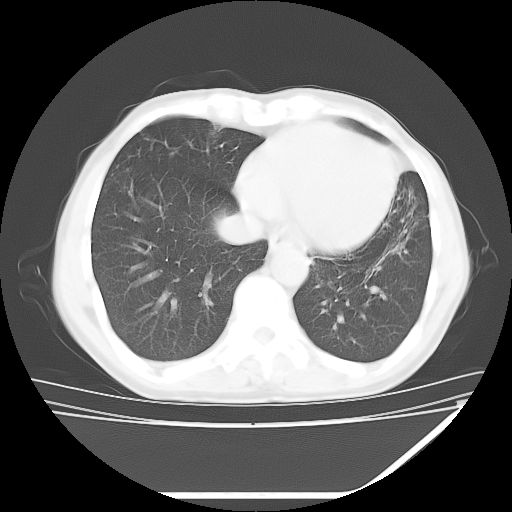

男,59岁,“结核性胸膜炎”30余年,胸部经常疼痛,多次x检查提示“肺部”炎症。腹部疼痛5日,b超提示:“肝内短管结石,余显示不清,建议进一步检查。”

两肺结核并右侧胸腔积液;脾脏、腹腔及腹膜后淋巴结结核[陈旧性];肝内胆管结石

胸部腹部都是结核(双肺。纵隔淋巴结,肝脏,脾脏,肠系膜)